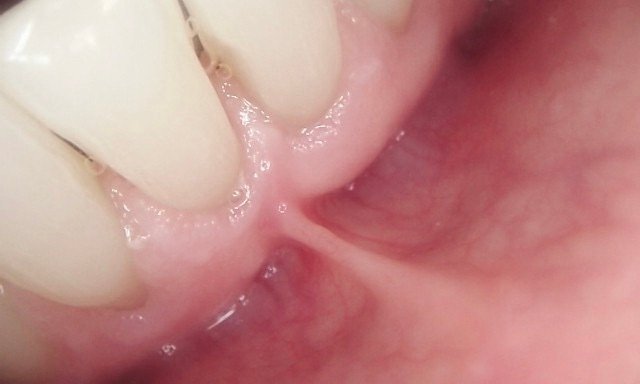

No Suture, No Bleeding

The laser automatically cauterizes the tissue as it works, acting as its own “healing seal.” This means you can leave our office with an instantly improved smile and zero stitches.